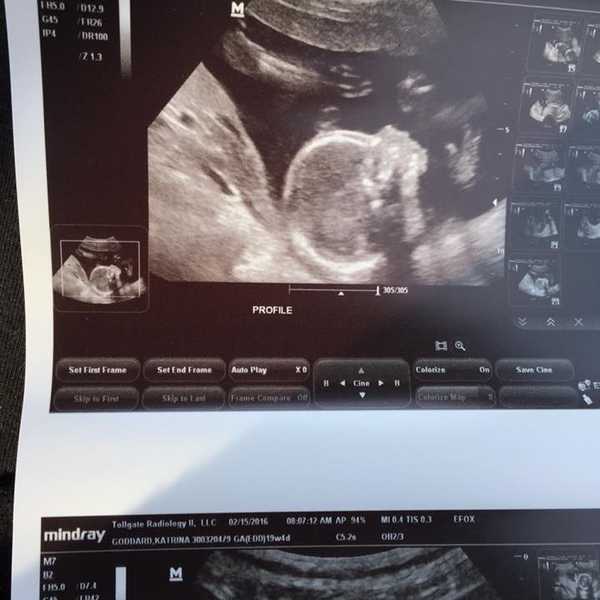

Nicole was the wonderful ultrasound tech that I had been consistently bothering for a few days. I was 36 weeks and 2 days pregnant and for the last month I had had major problems with low fluid levels around the baby to the point where my doctor had decided to send me to the hospital twice a week for fluid measurements and monitoring. That particular day, a Thursday, November 17, 2016, I just had a feeling that something was going to be different. I went to the hospital, was hooked up to the baby monitor for an hour and over that time I slowly realized that my little boy wasn’t as active as he usually was. The head nurse, Julie, came in and looked at my readings and as she did so, I told her that I thought my fluid levels had dropped more. She shook her head and told me to go and see Nicole for my ultrasound. It took Nicole all of two minutes to confirm what I had already thought- my fluid levels were nearly non-existent and because of that, my son’s activity level had also dropped drastically.